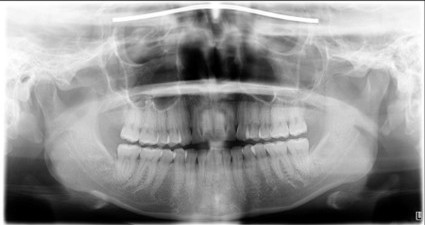

| 主訴 | 膿がたまてしまっていて痛い状態 |

| 状態 | 歯をとった瞬間に黄色い膿が吹き出た |

| 治療内容 | 根先部が破壊されてしまっていて、治療が難しい状態だったがマイクロスコープによる根管治療と、MTAセメントでの根幹充填により症状が緩和された。 骨再生因子を用いて骨を再生し、5ヶ月後には骨の再生が完了。セラミックによって審美的に補綴をして終了したケース。 |

| 料金 | 抗菌性歯内両方10万円、ファイバーコア2万円、ジルコニアクラウン12.5万円→14.5万円+税 |